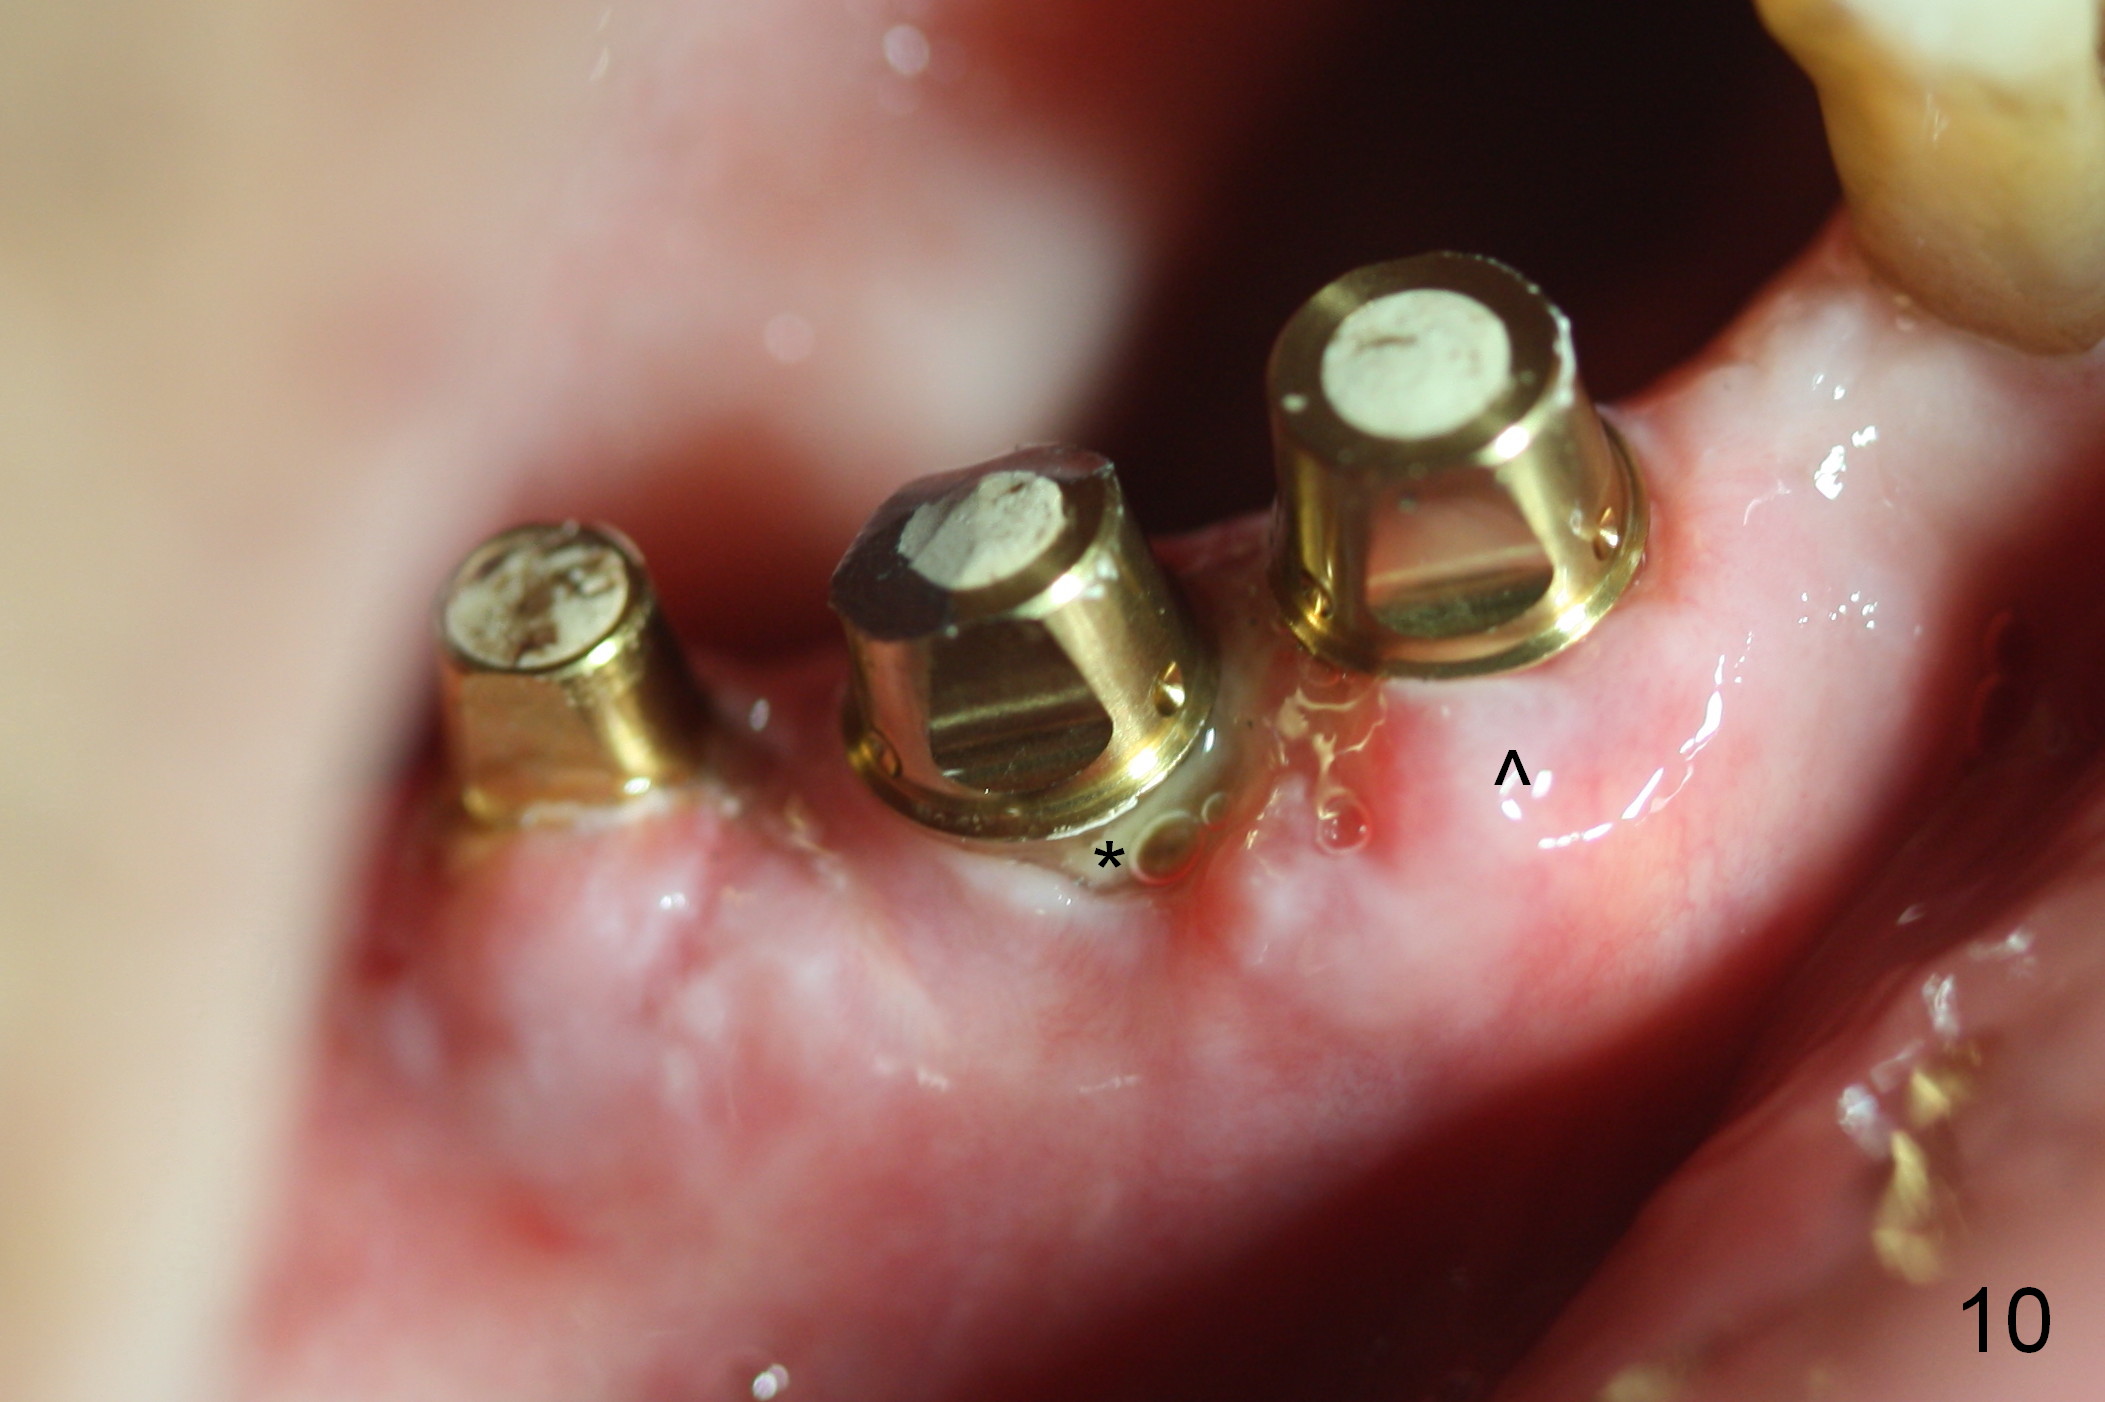

Eight days postop, the most anterior portion of the perio dressing is dislodged; the rest is stable (Fig.9). Since the patient has difficulty in coming to office, the perio dressing is removed. While the buccal gap of #27 has closed apparently (Fig.10 ^), that of #28 not (*). To prevent irritation from the abutments, a splinted provisional is fabricated (Fig.11 P). Perio dressing should have been re-applied buccal to the gap at the site of #28 or preferably the original perio dressing should have not been removed prematurely.